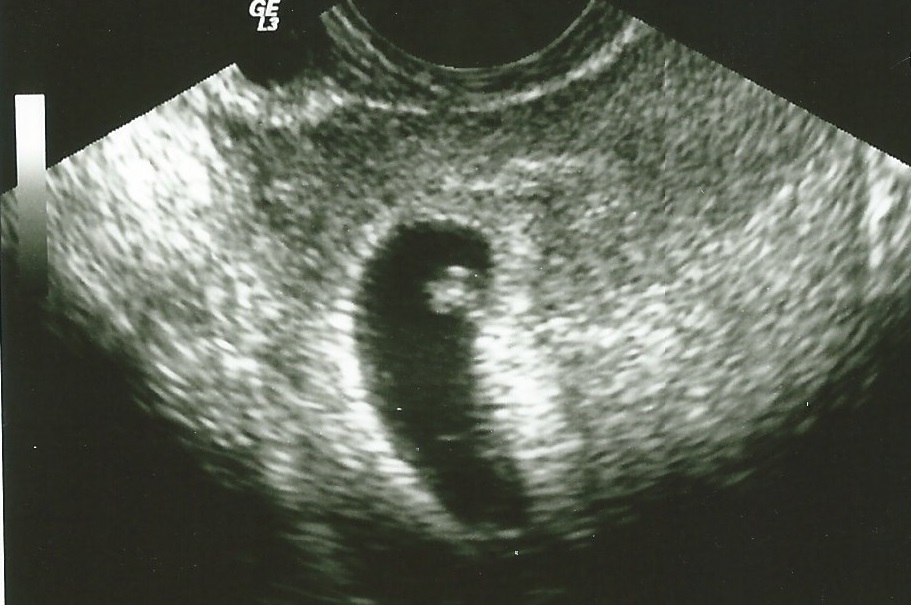

So I know a lot of us have had our first ultrasounds lately and you can add me to the list. I wasn't supposed to have it until Tuesday but I started having bad cramping today. Its the worst I have had and with all we've gone though to get here I'm a bit paranoid. My DH was wonderful about it all and called the RE so they brought me in early. We were able to see our little bean measuring just a few days behind but with a heartbeat of 115. The doctor we saw wasn't our doctor so he recommended we keep our appointment Tuesday. I am a bit more relieved but still nervous because I know it is still early.

Below is the picture.